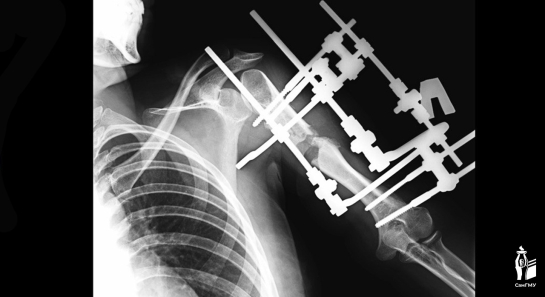

Пациентке поэтапно вырастили свою собственную кость.

В Самарской области хирурги провели уникальную операцию. В клинике СамГМУ врачи удлинили руку девушки на 13 сантиметров.

В раннем возрасте пациентку настигла тяжелая болезнь. Острый гематогенный остеомиелит разрушил зону роста в верхней части плеча, из-за чего разница между руками достигла 15 сантиметров. Это не только вызывало косметический дискомфорт, но и ограничивало выполнение простых повседневных задач. Медики решили удлинить руку.

- Удлинение верхней конечности на такую большую величину за одну операцию — смелое решение, мы понимали, что есть риски осложнений. Для удлинения на такую большую величину подходит метод Илизарова, при котором поэтапно выращивается своя собственная кость, - пояснил врач Никита Лихолатов.

Как пояснил медик, обычно такое растяжение у детей проводится на 1 мм в сутки. Костные фрагменты раздвигаются, между ними образуется мягкая костная мозоль, которая в дальнейшем перестраивается в кость. Но так как девочке было уже 17 лет, процесс растяжение проходил медленнее обычного - менее 1 мм в сутки, чтобы избежать повреждения мягких тканей.

Пациентка носила аппарат долгое время, могла учиться и заниматься повседневными делами. Недавно аппарат сняли, и теперь она проходит реабилитацию. Врачи успешно устранили косметический дефект и восстановили функциональность руки.

фото: СамГМУ